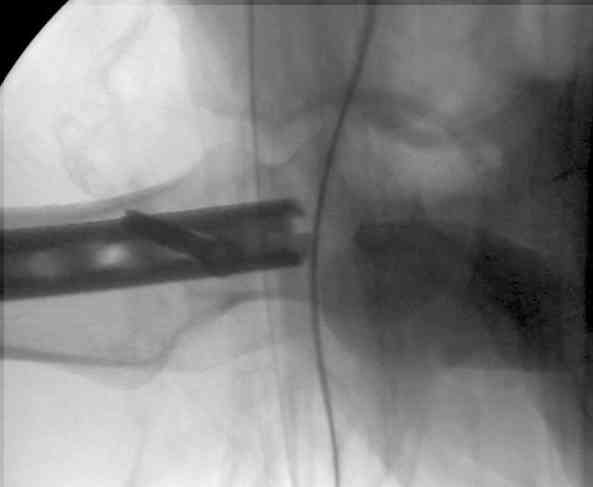

СМ> Что, реально изогнуть титановый гвоздь, не сломав его?

Конечно. Чтобы не сломать, лучше проложить в тиски сразу ниже отверстий полоску металла, чтобы там создалась концентрация напряжений при изгибе, а не на уровне отверстия.

Вот несколько. С тисками и трубой на днях сделаем.